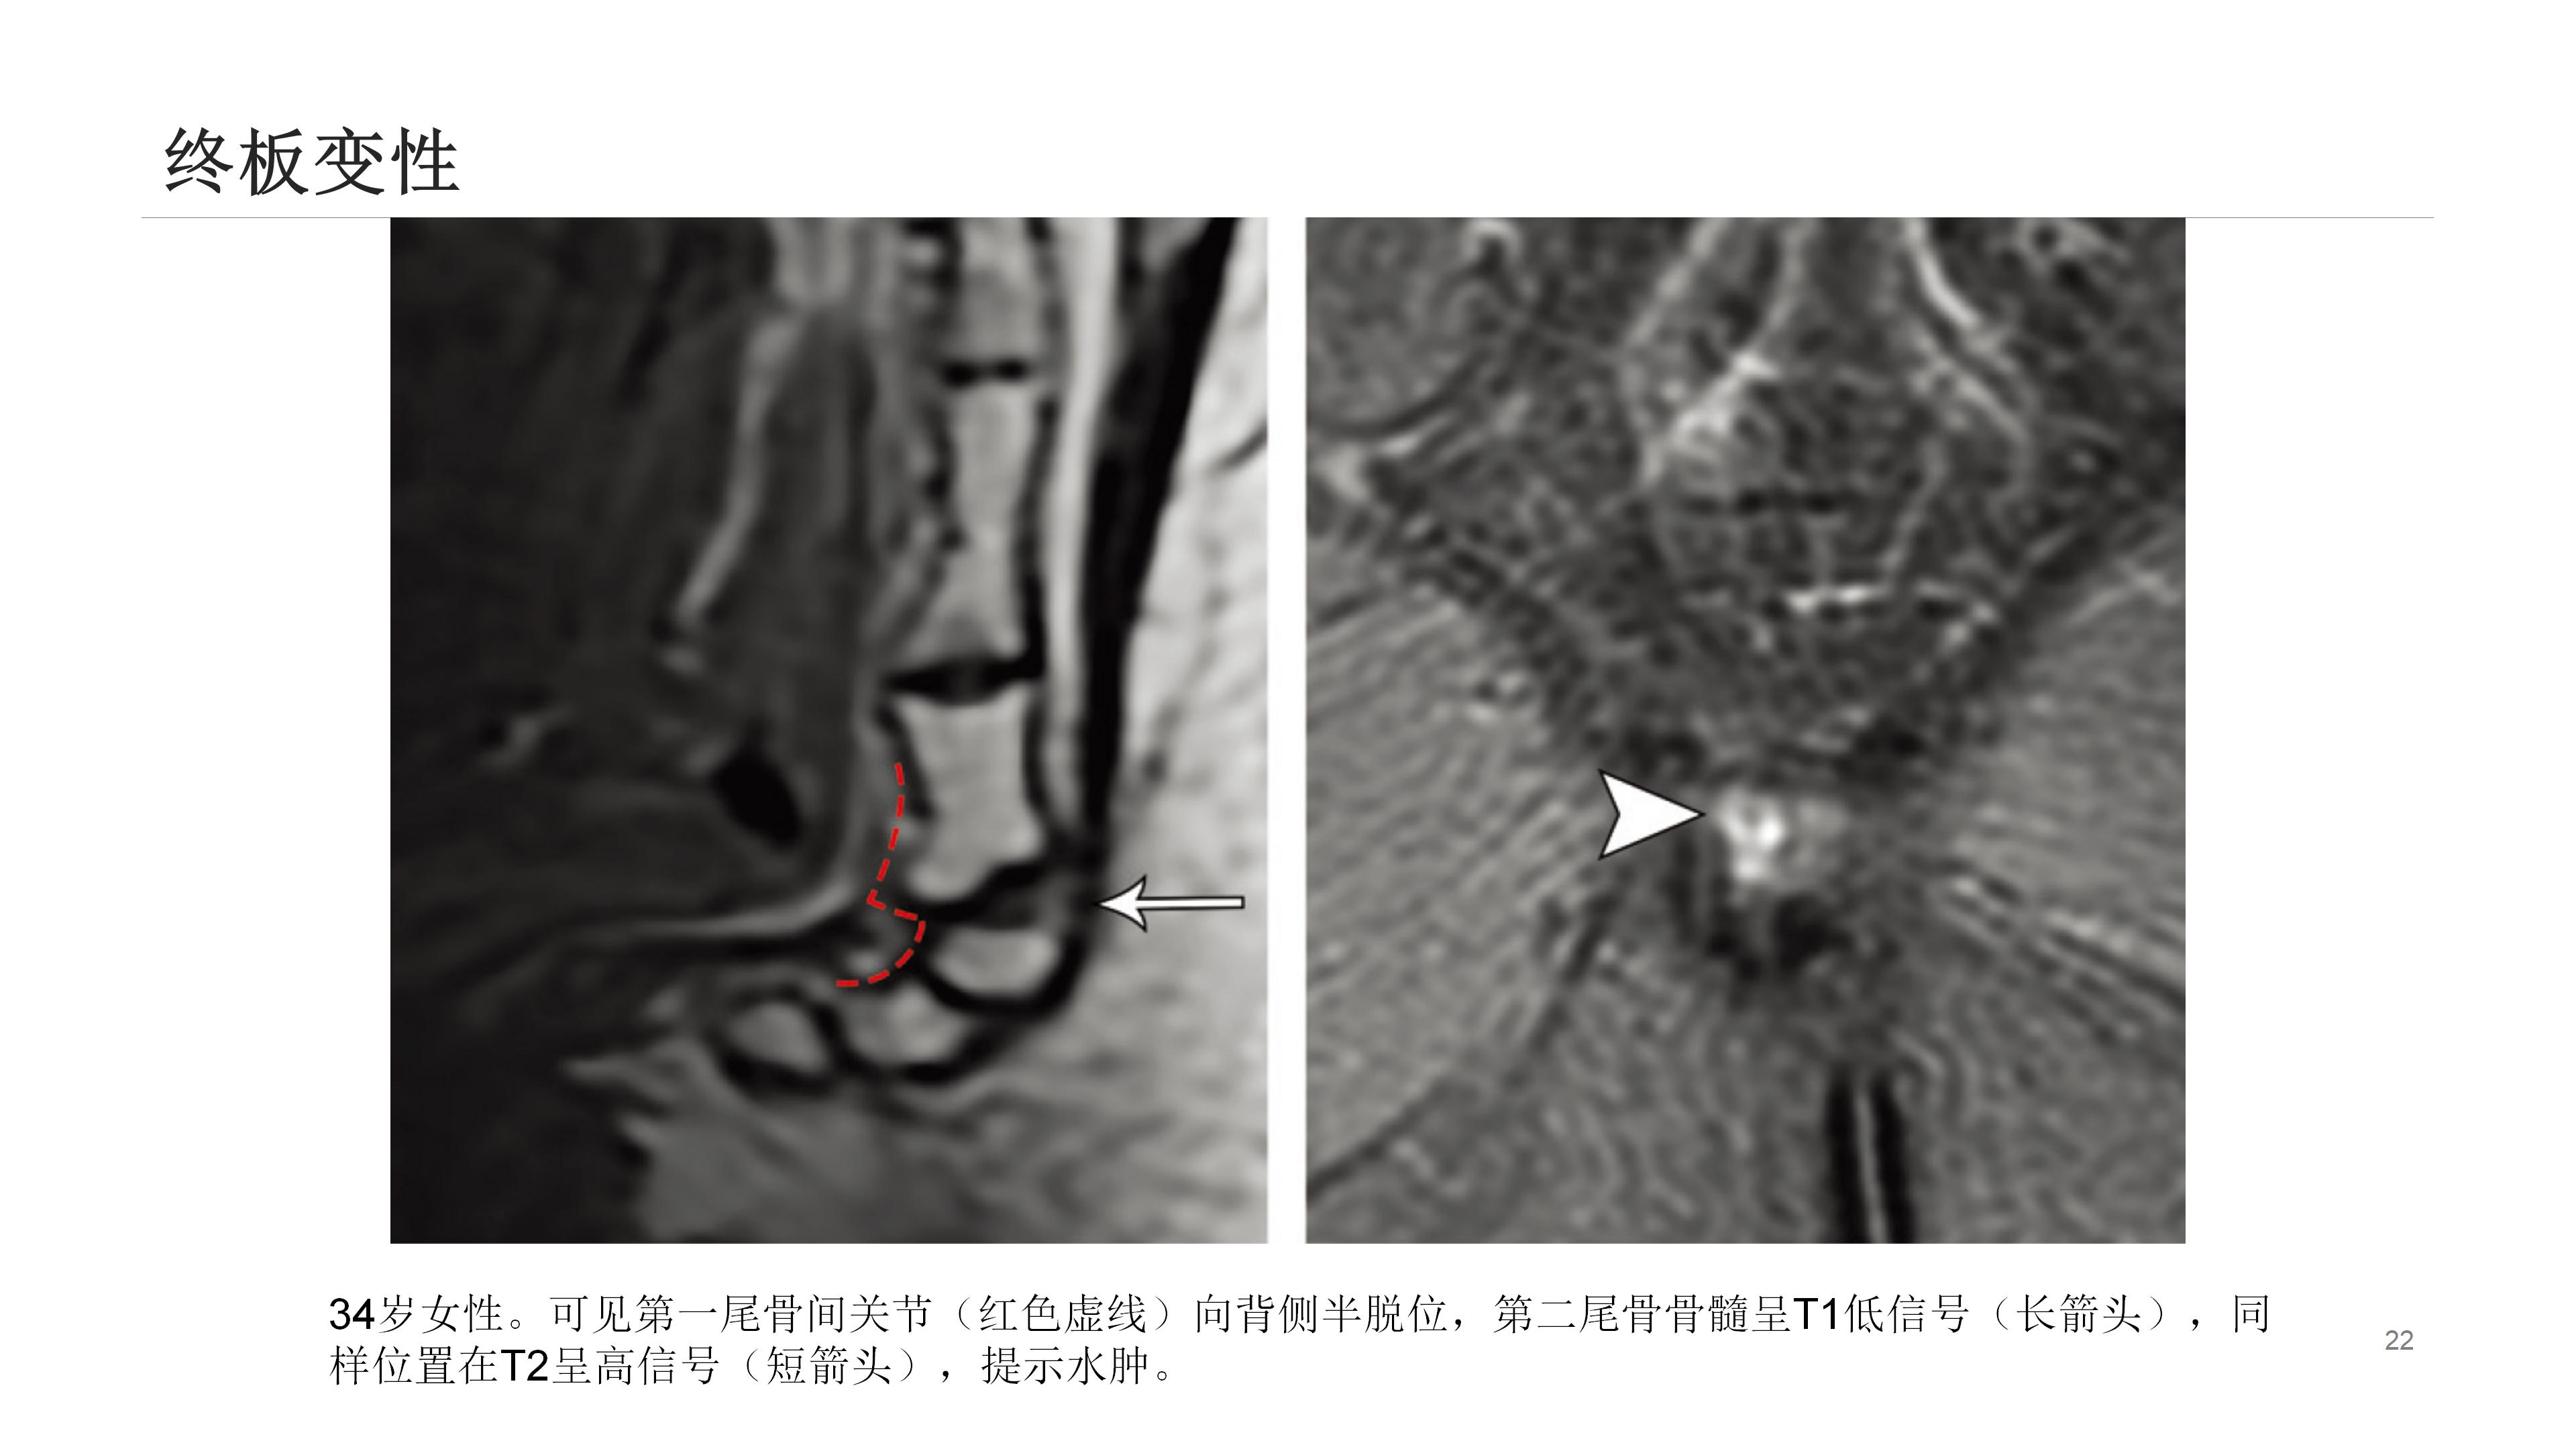

尾骨区域解剖结构复杂,众多结构皆可能引发该区域疼痛。影像学能出色呈现其解剖学特点,辨别受累结构可指导临床处置。尾骨疼痛乃常见临床症状,却难以评估和治疗。

通常,尾骨疼痛多在创伤后出现,初始静态平片检查可能正常,而动态平片(站立位及坐侧位平片)或可观察到异常尾骨移动,以此解释疼痛来源。